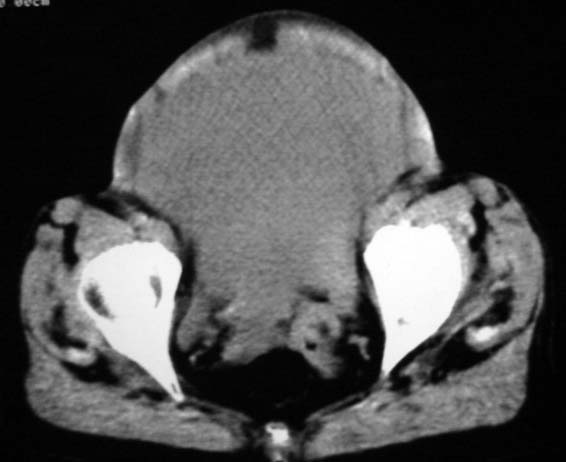

女,75岁,腹部胀大半年余,无其他症状。

考虑来源与卵巢的巨大囊腺瘤或囊肿。

考虑来源于卵巢的巨大囊腺瘤;如果是单纯囊肿不知其前部的更低密度区怎么解释?

考虑来源卵巢巨大黏液性囊腺瘤。